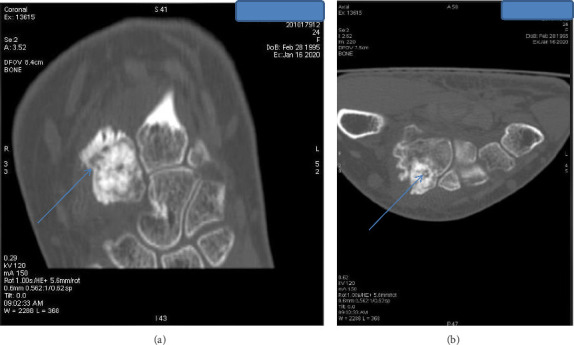

Osteoid osteomas predominantly occur in the cortices of long bones, with the femur and tibia being the most commonly affected sites. However, they can occasionally present in atypical locations, such as the carpus, which can lead to diagnostic confusion with other conditions. This case report details an intraarticular osteoid osteoma in the trapezoid bone. Initial evaluations, including standard radiographs, joint ultrasound, and wrist MRI performed twice, initially pointed toward a diagnosis of wrist synovitis. This case underscores the diagnostic challenges posed by atypical presentations of osteoid osteomas. Given the edema present in the carpal bones alongside the synovitis, we performed a hand CT scan, which raised doubts about the appearance of the nidus and histopathological examination confirmed the diagnosis. Clinical symptoms, including pain and functional limitations, were completely resolved following surgical excision.